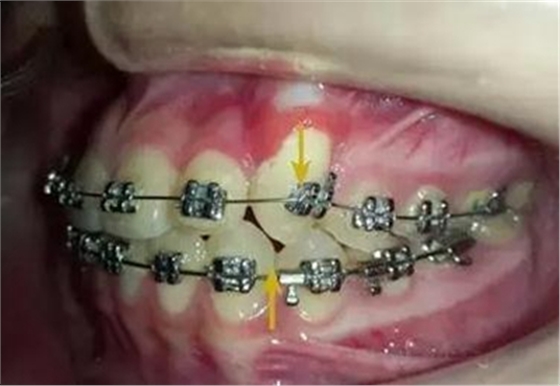

幾個月后,換上不銹鋼方絲,側(cè)切牙遠中彎制了一個內(nèi)展彎,避免了尖牙遠中移動時與弓絲形成頜干擾。

考慮了一下沒有采用其他輔助裝置和種植支抗,還是采用輔弓增加支抗,經(jīng)濟適用,也便與操作,0.8不銹鋼絲彎制,進行熱處理,增加其彈力。

結(jié)扎固定后開始牽引尖牙向遠中,

兩個月后效果還是比較明顯的。